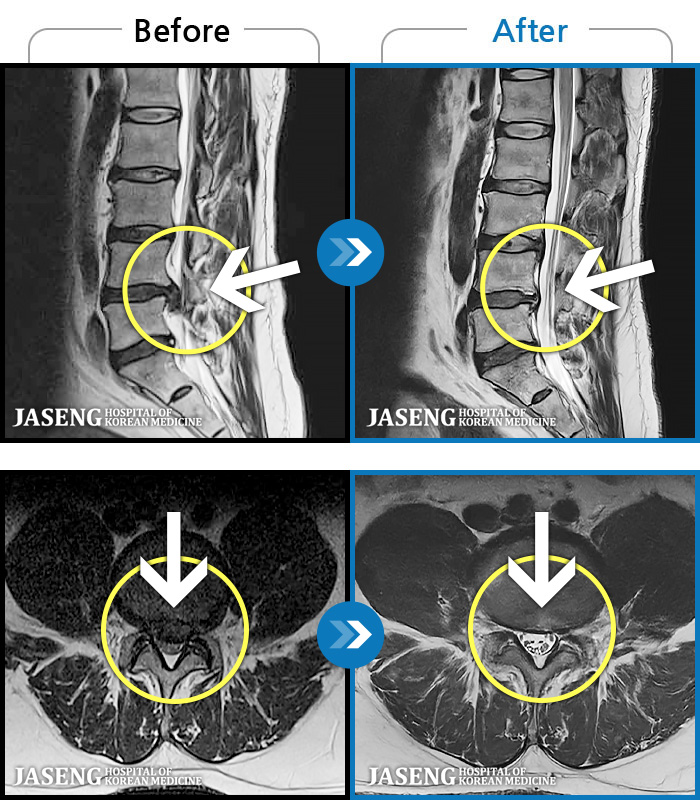

[ؿ] 24.10.10~25.04.23

ȯںп Ǹ ǿ ԿǾ, ο ġ ۿ Ƿ ġḦ Ͻñ ٶϴ.